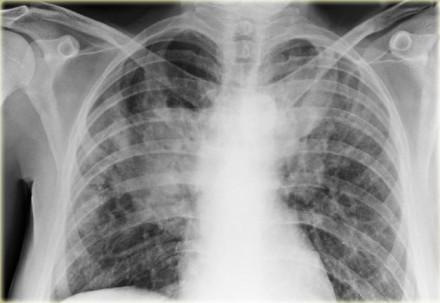

Older age and female sex are some of the factors associated with early-onset interstitial lung disease (ILD) in rheumatoid arthritis (RA), reveals a study.

This retrospective observational study utilized health services data from Ontario, Canada and identified RA cases between 2000 and 2020 using the Ontario Rheumatoid Arthritis Database. RA-ILD diagnosis required repeat physician visits for ILD. Early RA-ILD was defined as onset within 1 year of RA diagnosis.